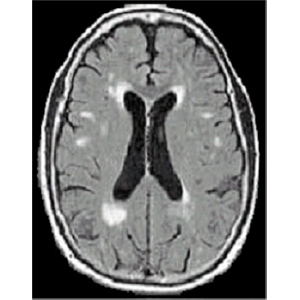

EATING AND SWALLOWING IN ALHEIMER’S DISEASE   Alzheimer’s disease is associated with problems in brain networks that store the memories of how to use and manipulate tools. This problem can impact how these individuals eat and swallow. More research needs to be done to improve functional independence in people with a diagnosis of Alzheimer’s disease.   Summary: Dementia is defined as a decline from a...